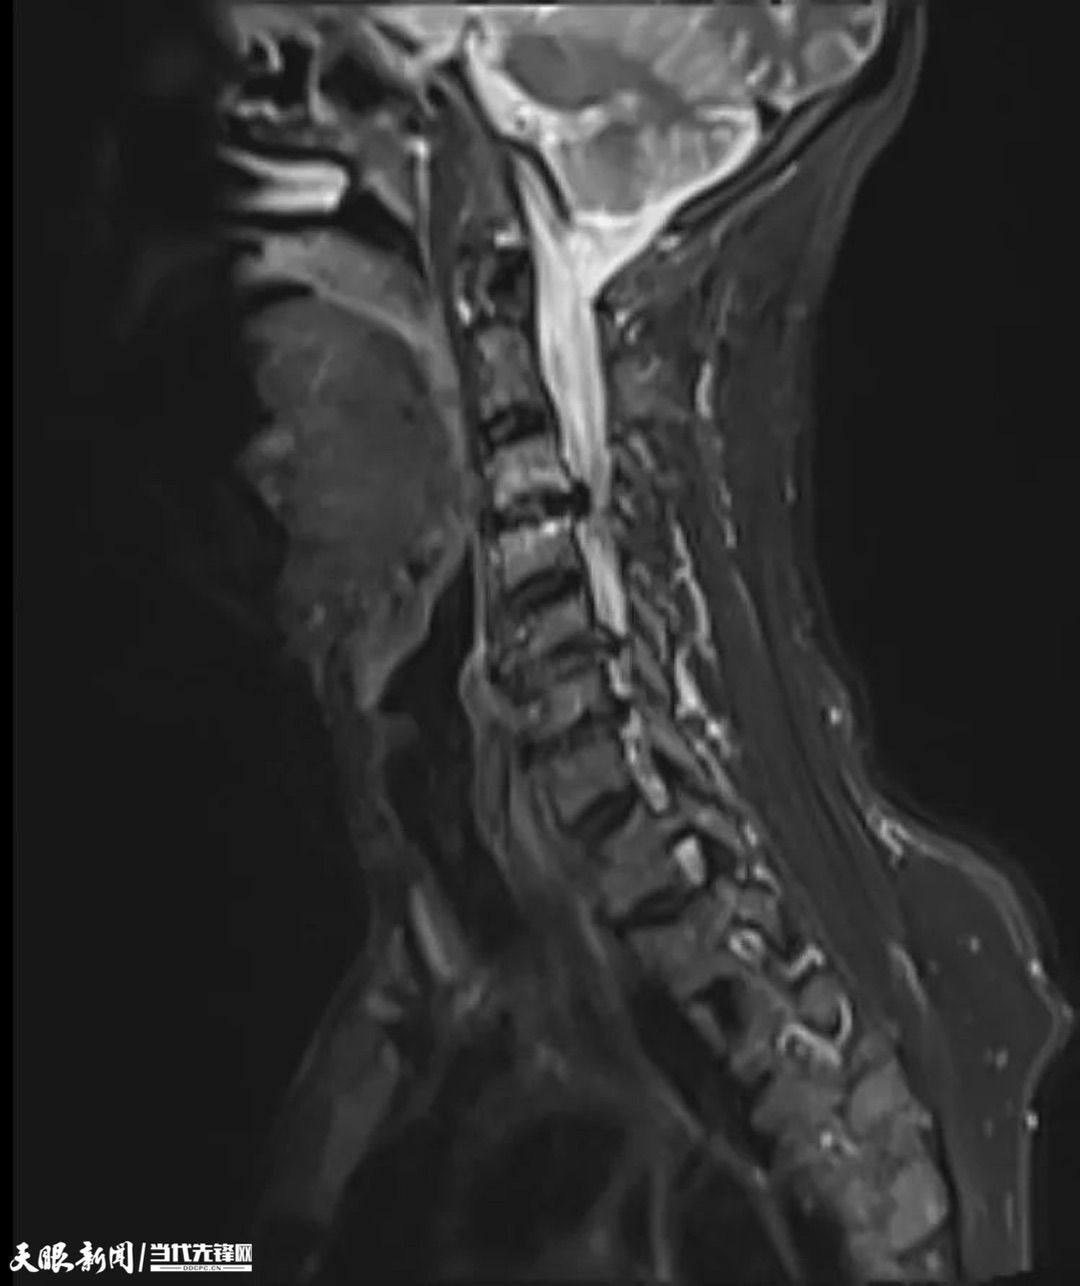

转院后,市中医院副院长、骨伤科主任医师孔维军和骨伤科主任陈在飞第一时间查房看望王某。在排除颅脑疾病的前提下,检查发现他患有严重的脊髓型颈椎病,颈脊髓损伤严重,并且颈椎椎管狭窄,脊髓被压扁变形,几乎只剩一条细缝,需要尽早手术解除压迫,如果压迫不解除,可能会终身瘫痪。

术前MRI